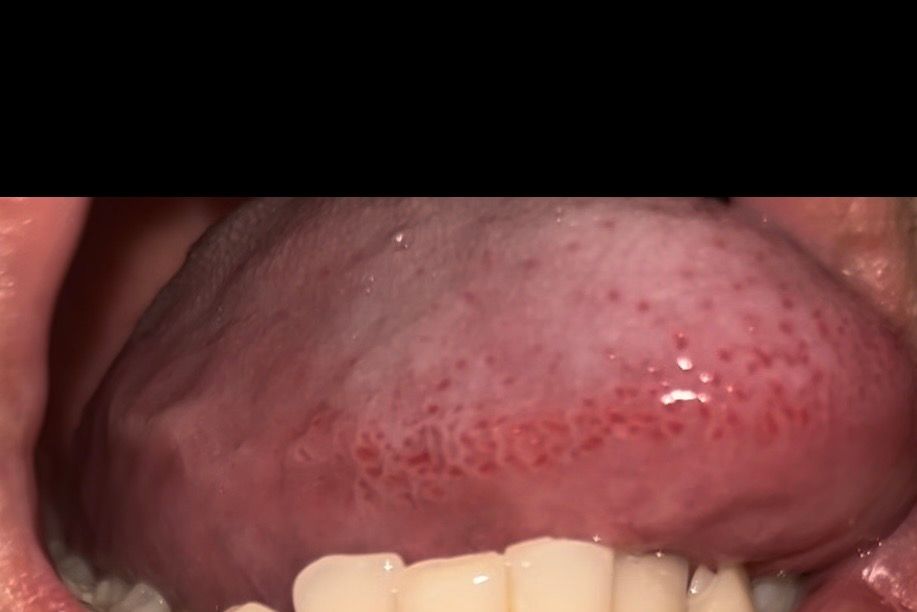

요즘 공부하느라 잠 많이 못 자서 그런지 아니면 깨물었던 건지 구내염이 생겼네요 찾아봤는데 편평태선 이라는 것도 있더라고요 혀 옆면에 붉은 반점 같은게 저렇게 있는데 맞나요? 뭐죠 저게ㅜ 어릴때부터 있었던 거 같아요 또 그냥 구강 상태 괜찮은건가요 20대 초반 흡연자입니다ㅜ 걱정되네요

• 4번 째 사진